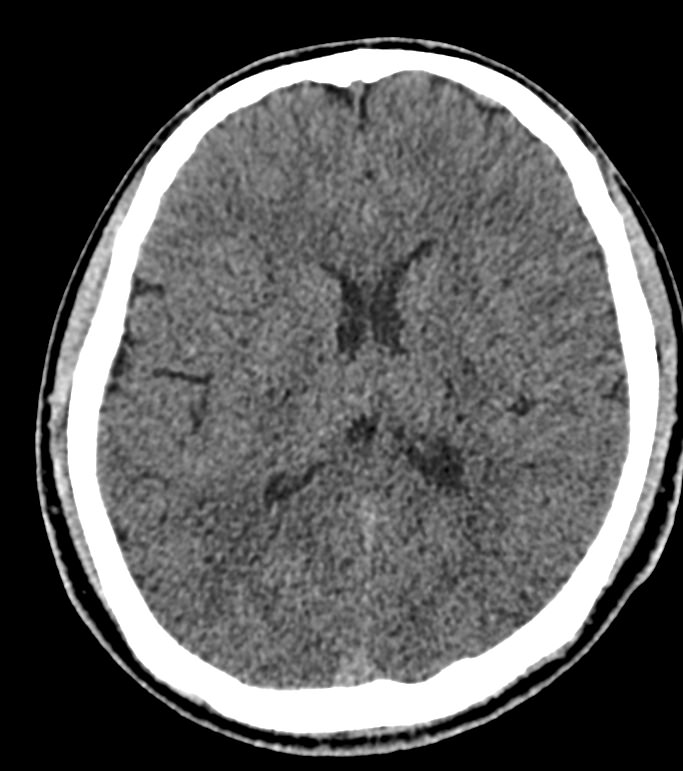

Мультиспиральная компьютерная томография головного мозга относится к лучевым методам диагностики заболеваний центральной нервной системы.

Методика построена на использовании проникающей способности рентгеновских лучей, которые в различной степени поглощаются органами и тканями (степень поглощения зависит от их плотности), благодаря чему можно получить подробные изображения внутренних органов. Во время исследования трубка томографа вращается вокруг пациента и производит снимки поперечного сечения, что позволяет детально визуализировать кости черепа и все структуры головного мозга.

Наши медицинские центры оснащены новейшими мультиспиральными компьютерными томографами экспертного уровня TOSHIBA AQUILION в различных модификациях. Аппараты снабжены увеличенным количеством сверхчувствительных детекторов, что позволяет при сканировании выполнять от 64 до 128 срезов поперечного сечения с минимальной толщиной среза от 0,5 мм. В результате получаются изображения исследуемой зоны в мельчайших подробностях, которые затем с помощью инновационных цифровых приложений преобразуются в трехмерные пространственные модели головного мозга для более точной диагностики.

Нативное сканирование подходит для диагностики дистрофических изменений головного мозга, определение острого нарушения мозгового кровообращения, как ишемического, так и геморрагического характера, а также отслеживание последствий подобных состояний при прохождении реабилитации.

Что можно выявить на КТ головного мозга?

- нарушения мозгового кровообращения (имеются в виду как геморрагические, так и ишемические инсульты);

- отек мозга;

- кисты, кистозно-атрофические изменения

- смещение внутренних структур головного мозга.